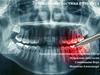

РентгенографияЭтот метод широко применяется для того, чтобы выяснить особенности строения

зуба, степень развития болезни и результаты лечения, которое проводилось ранее. В том случае,

когда необходим снимок коренного зуба нижней челюсти проводят внеротовое

рентгенографическое обследование. Для того, чтобы получить снимок остальных зубов

используют внутриротовой способ.